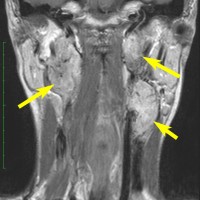

左は1991年,右は2006年のMRI画像です。15年間で腫瘍のサイズは変わっていません。

1991年に50代の女性にみつかったものでした。黄色に示したルートで摘出できないわけではありませんが,右後頭部が腫れてきたという訴えとホルネル症候,軟口蓋麻痺しかなかったので,何も治療しないでほっておきました。2016年まで25年間観察し続けました。症状の悪化は全くなく元気に暮らしておられます。グロームス腫瘍はある一定の年齢になると増大しないという性質を持っている良性腫瘍です。これを大々的な頭蓋底外科手術で摘出するするという愚を犯してはなりません。

遺伝歴があり30代くらいです。黄色の矢印で示す右側はglomus vagale,左側は上がglomus jugulare、左下がglomus caroticumです。教科書に載せたいくらい典型的な部位に発生しています。無症状ですからもちろん治療はしません。6年くらい経過観察していますがほとんど増大もしません。